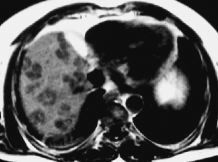

Lesiones benignas y metástasis hepáticas de adenocarcinoma colorrectal en RM: aplicación de la secuencia turbo spin echo T2 para su diferenciación

Magnetic resonance imaging of bening lesions and liver metastases derived from colorectal adenocarcinoma: differentiation by means of T2-weighted turbo spin-echo sequences